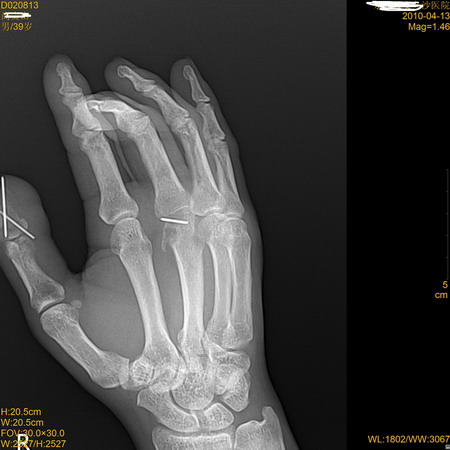

标题: X7184:内固定术后,1月余!

是废用性骨质疏松?还是缺血性坏死?

多发骨折内固定术后,废用性骨质疏松

右手拇指末节及第三掌骨远端钢针内固定术后,第三掌骨远端局限性骨吸收改变伴关节间隙狭窄。

第三掌骨头关节内骨折复位差畸形愈合